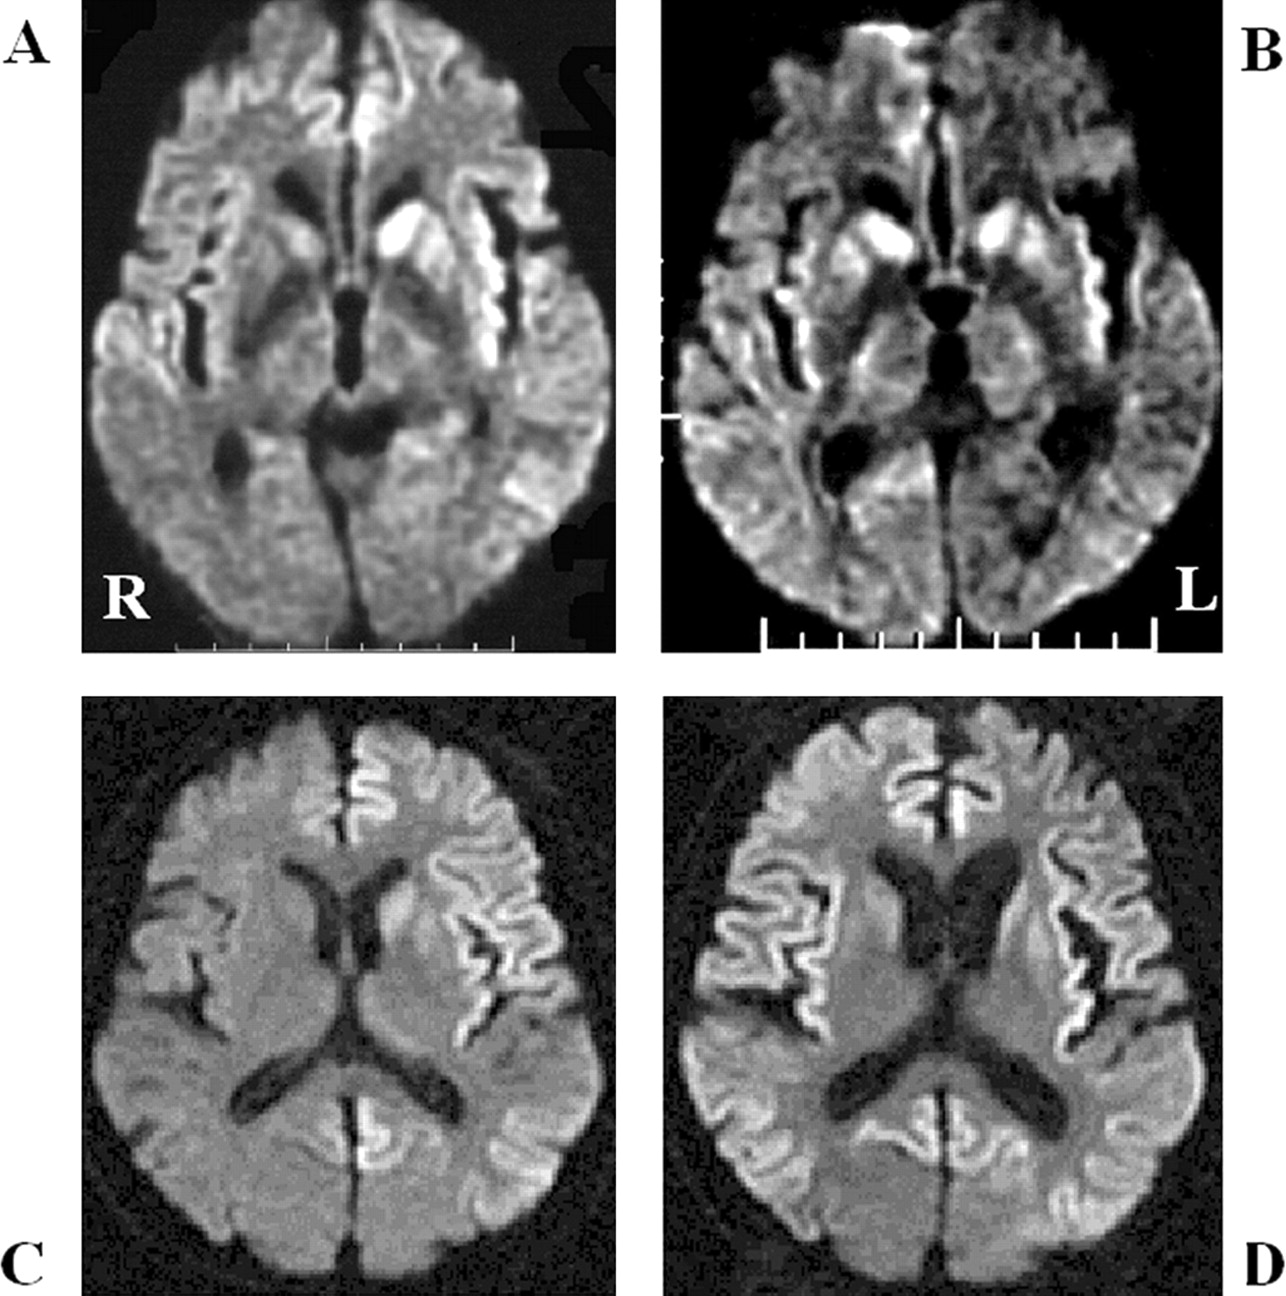

酒后驾驶是在26日检查库贾氏症患者发病后3到25周平均持续时间为10.7周。24库贾氏症患者表现出高强度脑损伤的驾车考试。两个观察者,醉酒驾车的库贾氏症诊断的敏感性为92.3%。interobserver协议率为100%。3例(12.5%)显示只在尾状头和硬膜损伤,10例(41.7%)患者显示线性损伤只有在大脑皮层,和11例(45.8%)患者显示病变基底神经节和大脑皮层(图1)。其中,只有三个病人(12.5%)显示,丘脑病变。没有病人显示高强度在小脑病变。高强度损伤在驾车之前出现脑萎缩。病变包括纹状体初并不总是对称的但是后来对称(图2),尽管对称的纹状体病变是众所周知的在库贾氏症。11在某些情况下,高强度损伤与连续驾车并不总是进展的疾病,而有时信号强度降低了疾病进展的一些病变。在某些情况下,皮质高信号强度不同,解剖分布(图3)。在终端阶段与深刻的脑萎缩,高强度损伤变得不清楚。T2I DWI-examined 26日在23日检查病人,但T2I扫描被排除在外,因为低质量由于运动构件。一位观察家认为11 22患者阳性(50.0%),而另一个观察者认为8阳性(36.4%)。interobserver协议率为68.2%,低于酒后驾车(p< 0.005)。在这两个观察者,醉酒驾车是比T2I更敏感(p一个观察者,< 0.005p另一个观察者p < 0.0005)。天赋是17 26患者的检查。一位观察家认为10 17例阳性(58.8%),和另一个观察者认为7是积极的(41.2%)。interobserver协议率为82.4%,也低于酒后驾车(p< 0.05)。醉酒驾车是比天赋更敏感(p一个观察者,< 0.01p另一个观察者p < 0.0005)。我们在图4一个例子中,只有醉酒驾车可以检测高强度异常病变。

图4。比较显眼的克雅氏病疾病变化相同的病人在不同的核磁共振序列。t2加权成像(A)和fluid-attenuated反转恢复成像(B)显示正常的结果,和diffusion-weighted MRI (C)展示了高强度在大脑皮层病变。